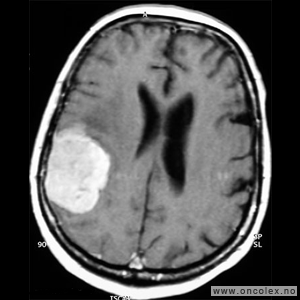

Glioblastomer

Glioblastom er den vanligste hjernesvulsten hos voksne, og cirka 220 norske personer får denne diagnosen hvert år. Samtidig er det en av de mest aggressive svulsttypene hvor i praksis alle pasienter på ett eller annet tidspunkt vil oppleve tilbakefall. Cirka 60 % av pasientene er menn og halvparten av pasientene er over 60 år. Behandling vil oftest være en kombinasjon av operasjon, strålebehandling og cellegift. For en del pasienter kan det være aktuelt å delta i studier med utprøving av ny behandling.